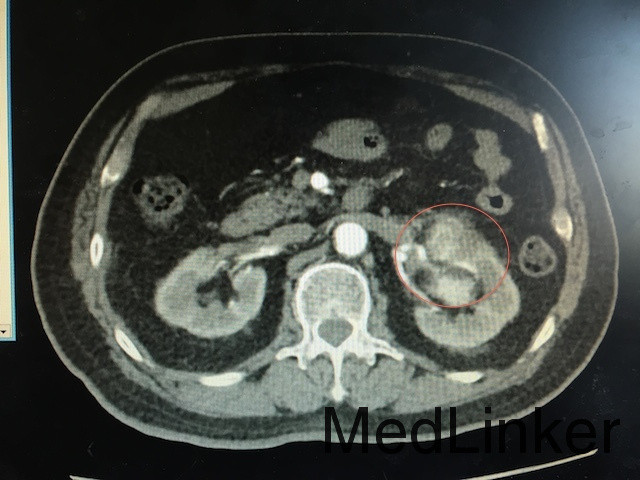

查体:左肾区叩痛可疑阳性 辅助检查:泌尿系CT平扫+强化如下图所示:左肾下极可见软组织密度团块影,突出肾轮廓并累及肾窦,大小约为6.6*6.1*5.7cm,动脉期呈不均匀强化,可见左肾动脉分支血供。

诊断:肾占位(肾恶习肿瘤可能性大) 治疗:肾癌根治术

随访:肾及肾周包膜切除,病理回报为肾透明细胞癌 讨论:肾恶性肿瘤主要与肾错构瘤鉴别,后者B超可见脂肪密度高回声,CT平扫为脂肪密度,CT增强强化比肾恶性肿瘤更明显。